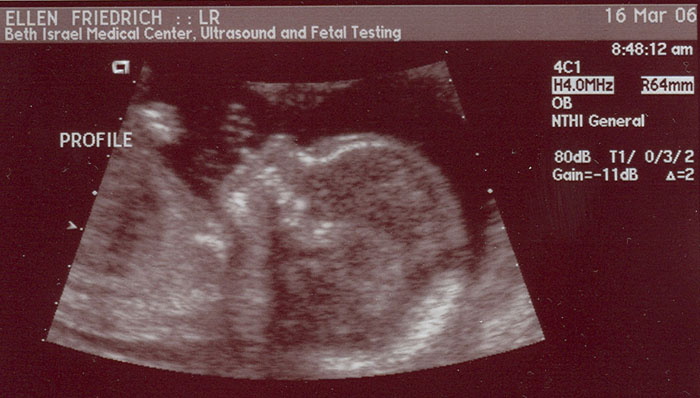

Making progress - 20 weeks- March 16 - 2006

A head